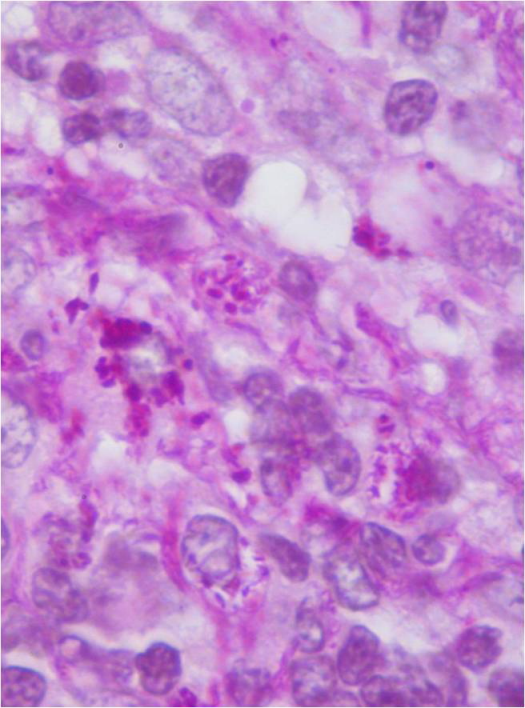

The analyses showed a sedimentation rate of 112 mm/h, leukocytosis (13,300 cells/µl/mm3 (90.9% N; 5.8% L)), C-reactive protein of 112,1 mg/L and increased γ globulins (25.3%) with elevated IgG (21 g/L) on protein electrophoresis. The remaining analytical evaluation was normal, including infectious serology (HIV, Borrelia burgdorferi, Mycoplasma pneumoniae, among others), autoimmunity study, pro-thrombotic factors and angiotensin-converting enzyme (ACE). The cranial and cervical MRI revealed a T2 hypersignal focus on the right cerebellum with restriction diffusion and correspondence on the apparent diffusion coeficiente (ADC) map, in relation to a likely acute ischemic vascular lesion. It also showed a difuse C3-C6 hypersignal on T2 related to a focus of edema/mielomalatia, in association with osteo-degenerative changes of the cervical spine. The spinal fluid output pressure on the lumbar puncture was within the normal range, as well as the cytochemical, microbiological and infectious serology exams. Considering the possible diagnosis of neuromyelitis optica (NMO), also known as Devic’s disease, an assay to detect NMO-IgG or aquaporin-4 antibodies was performed with a negative result. The Mantoux test was also negative. The thorax CT showed the existence of multiple small axillary and retrocrural adenopathy, which were then submitted to an image-guided biopsy. The histopathological analysis indicated the intracytoplasmic presence of multiple periodic acid-Schiff-positive bacilli, consistent with a Tropheryma Whippelli infection, as well as the absence of acid-alcohol resistent bacillus (BAAR) (Figure 2 [Fig. 2]). The PCR (polymerase chain reaction) detection of Tropheryma Whippelli on peripheral blood was negative. In light of these findings, the past medical history of the patient was further investigated, and he confirmed an episode of a rare infection manifested only with fever (he did not know the name of the disease), which was diagnosed in France, where he used to reside, and for which he was treated with sulfamethoxazole 800 mg and trimethoprim 160 mg for approximately 3 years.

Figure 2: Ganglionic biopsy, PAS